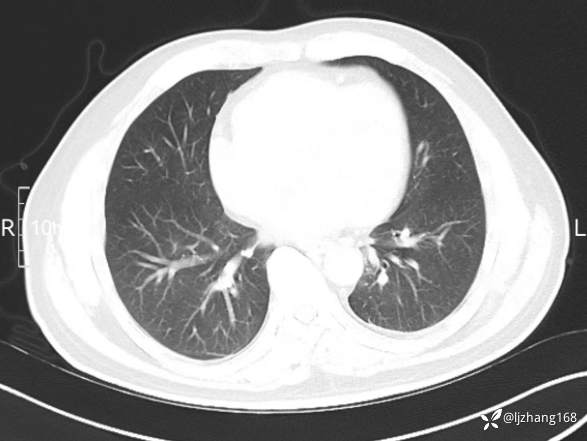

辅助检查:糖化血红蛋白12.3%。肺炎支原体IgG、IgM、呼吸道合胞病毒均未见明显异常。胸部CT:右肺上叶阻塞性肺炎。